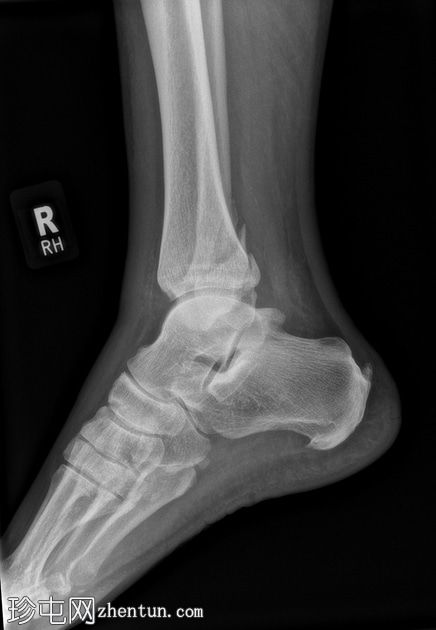

2.jpg

侧面

腓骨下端轻度螺旋形骨折,位于下胫腓联合水平(Weber B),骨折移位,伴有轻度软组织肿胀。

踝关节内侧间隙增宽6毫米(正常值<4毫米),胫腓间隙增宽,胫腓重叠减少,这些表现提示胫腓联合损伤和踝关节不稳定。

踝关节内侧软组织阴影,提示内侧副韧带损伤。

后踝(踝骨)骨折轻微移位。

可见腓籽骨。

足底跟骨骨刺。

可见跟腱末端钙化性病灶。